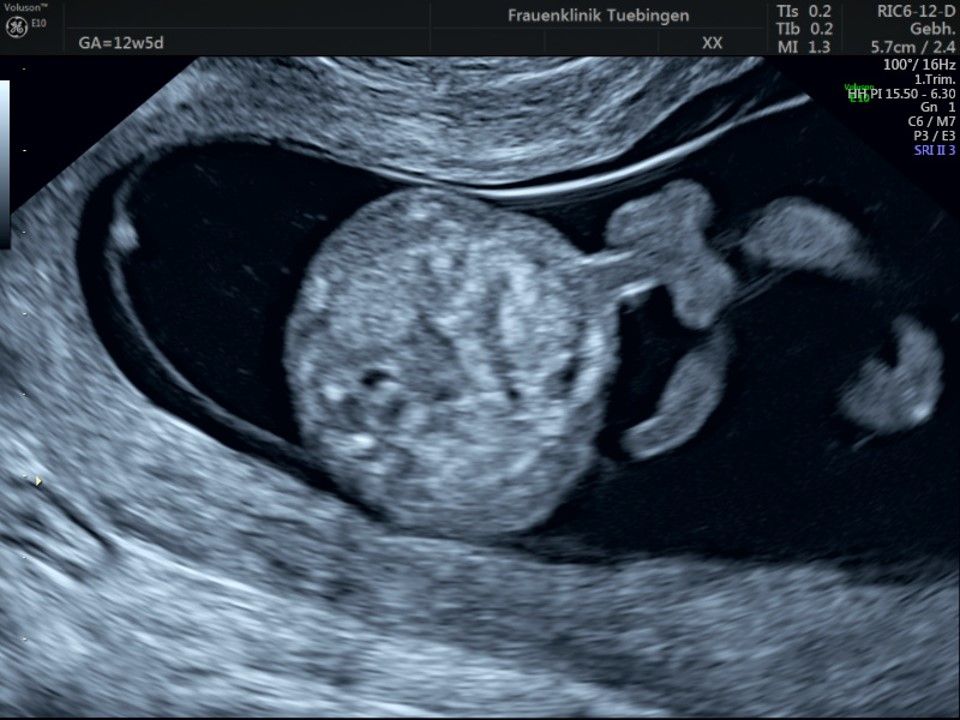

Im Rahmen des Ersttrimester-Screenings untersuchen wir die Organe des Feten mittels Ultraschall. Dabei machen wir auch gerne ein Bild für Sie.

Obwohl der Fet zu diesem Zeitpunkt erst zwischen 5 und 8cm groß ist, lassen sich bereits etwa die Hälfte aller schwerwiegenden Fehlbildungen erkennen bzw. ausschließen. Sollten wir eine Auffälligkeit sehen, werden wir mit Ihnen den Befund und das weitere Vorgehen ausführlich besprechen.

Die eigentliche Organuntersuchung findet um die 20.SSW (zweites Screening) statt. Das Ersttrimester-Screening und das zweite Screening sind sich ergänzende Untersuchungen und ersetzen sich gegenseitig nicht.